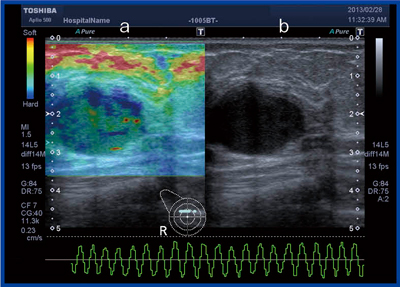

エラストグラフィでは,浸潤癌の組織構成や周囲の正常組織の収縮の様子もよく表現されている(図7)。

図7 症例2:エラストグラフィ(a)

b:Bモード画像,c:病理組織像